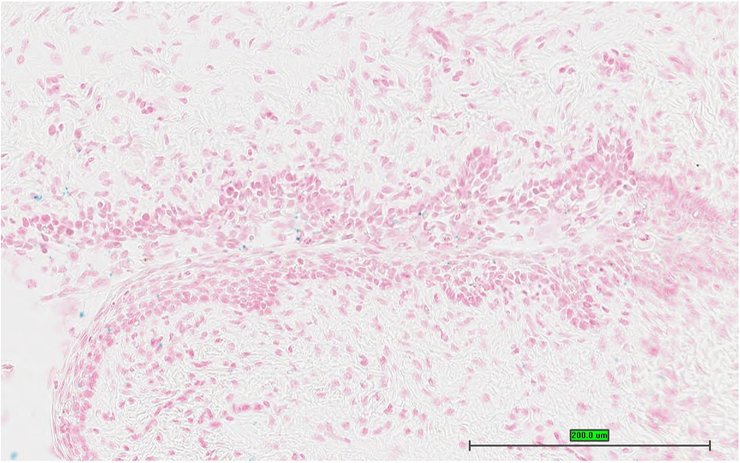

TS28: eye Present UC Davis_1856122

TS28: eye Present UC Davis_1856133

Specimen UC Davis_1856134: postnatal adult; Dzank1tm1b(KOMP)Wtsi/Dzank1+ (more )

TS28: eye Present UC Davis_1856134

TS28: eye Present UC Davis_1856135